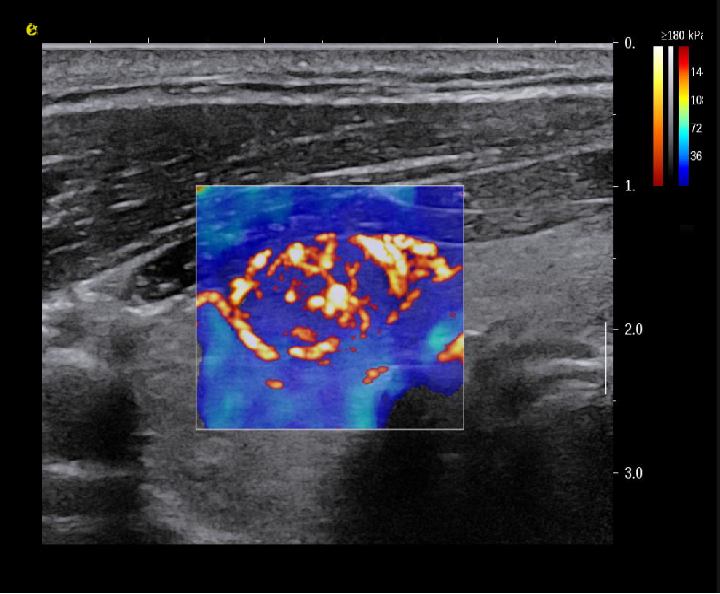

实时剪切波弹性成像

评估组织的软硬,并且提供定量数值,从而提示组织的良恶性。

恶性占位常常向周边组织进行侵润及扩散,二维很难观察到浸润部分的边界。使用实时剪切波成像能够对占位及周边组织进行硬度评估,通过颜色编码来区分不同组织的硬度信息,直观的观察占位组织的边界信息,更方便区分占位组织和正常组织的边界,准确评估消融范围。

左图病例所示:

钼靶阴性,B型发现非肿块病变

剪切波弹性成像见明确的硬度增高区域。

穿刺及手术病理结果:浸润性导管癌(IDC)

非肿块型病变:B型图像无法确认病变范围,E成像帮助发现异常区域和评估